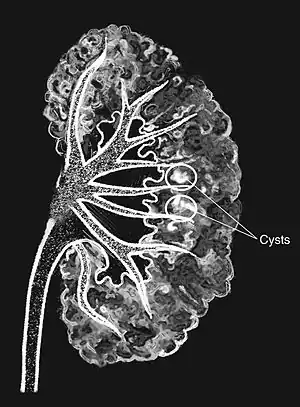

Medullary sponge kidney is a birth defect characterized by small cysts in the inner part of the kidneys.[2] Onset of symptoms; however, does not generally occur until late childhood or early adulthood.[2] Symptoms may include those or a urinary tract infection (UTI) such as burning with urination or kidney stone such as flank pain and blood in the urine.[2] Kidney failure is rare.[2]

The cause is unclear.[2] Most cases do not appear to be inherited from a persons parents.[2] The underlying mechanism involves dilation of the collecting ducts and tubules in the renal pyramids.[3] One or both kidneys may be involved.[2] Diagnosis may be supported by medical imaging.[2]

Classically, MSK is seen as hyperechoic papillae with clusters of small stones on ultrasound examination of the kidney or with an abdominal x-ray. The irregular (ectatic) collecting ducts are often seen in MSK, which are sometimes described as having a "paintbrush-like" appearance, are best seen on intravenous urography. However, IV urography has been largely replaced by contrast-enhanced, high-resolution helical CT with digital reconstruction.[9]